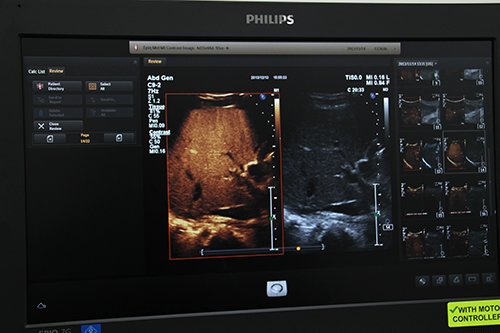

Auto Registrationで位置合わせしたフュージョン画像(左上)

新しく開発されたAuto Registrationは,指紋認証や顔認証と同様のアルゴリズムを用いることで,自動でCT/MRI/PET画像との簡単かつ高精度なフュージョンを可能にする。位置合わせを従来のような点や面ではなく,ボリュームデータの立体構造を基に行うことで,精度の高い位置合わせを実現。位置合わせは1分程度で調整でき,また,ボリュームで位置合わせを行っていることから,プローブの角度を変えた場合にも位置合わせをし直す必要がなく,位置ズレのないフュージョン画像をリアルタイムに得ることができる。位置合わせのアルゴリズムは,指紋認証技術を応用して肝内血管の立体構造で位置合わせをするVessel Baseと,顔認証技術を応用して肝表面の形状で位置合わせをするSurface Baseの2種類を実装。血管構造は人によって異なるため,それを基にしたVessel Baseでは非常に高い精度でフュージョンが可能となる。肝硬変などで血管構造の描出が困難な症例や,体格が大きく肝内まで音波が届きにくい症例などでは,Surface Baseに切り替えて位置合わせを行える。さらに,PercuNavは,従来は肝臓に特化していた機能であったが,前立腺や表在,頭蓋内血流などのアプリケーションにも適応を拡大した。前立腺がんの超音波ガイド下生検では,12個以上の組織標本を採取するランダムバイオプシーが一般的であるが,PercuNavを使ってMR画像とエコー画像のフュージョン画像をガイドにすることにより腫瘍組織への穿刺精度が向上し,2,3個の組織標本での診断が可能になるという。